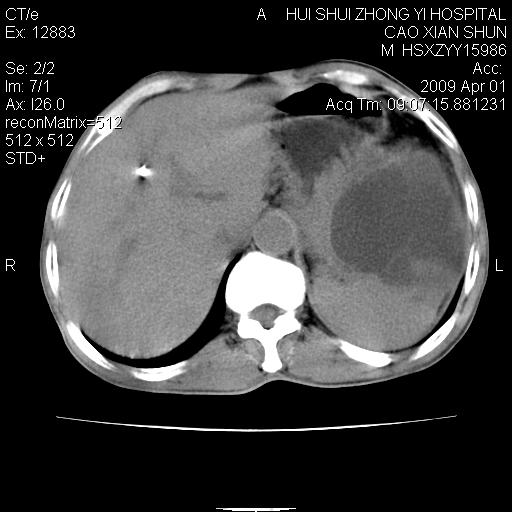

以下是引用随光逐影在2009-4-1 14:23:00的发言:[br]肝、脾多发低密度占位性病变,性质待定(不排除转移瘤可能);建议行进一步检查。

以下是引用liaoqiang在2009-4-1 15:53:00的发言:[br]考虑脾脏肿瘤或胰尾部肿瘤伴肝转移。建议增强。

以下是引用ydx_74在2009-4-1 15:18:00的发言:[br]肝、脾多发低密度占位性病变,考虑转移瘤或淋巴瘤